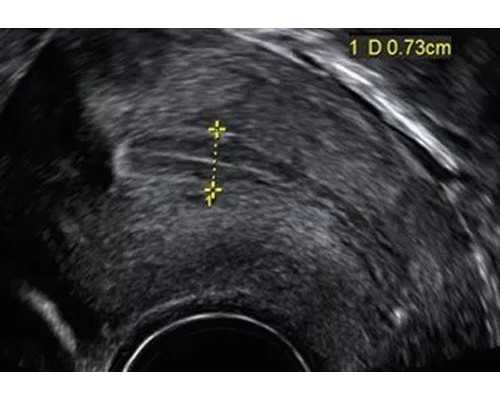

做试管婴儿术前检查项目会因人而异,一般费用在500010000元左右,较为全面的检查主要是男方精液、血液检查,女方生殖系统能力评估(甲状腺全套功能、性激素六项检查、子宫B超检查、阴道分泌物检查、HPV检查、支原体衣原体检查、卵巢功能评估AMH等)。

泰国试管婴儿技术优势有哪些?1、无痛取卵。在开展试管婴儿周期之前,首先会对女性进行全面地身体检查(子宫、卵巢、验血等)。子宫超声显像术便于了解女性子宫内环境;阴超检查是为了解子宫左右卵巢的卵泡数量;验血是了解夫妻双方的染色体是否发生异常等情况。医生在充分了解患者身体情况后,会针对每个患者的情况,在第一时间制定最合适的促排方案和安排促排卵,这也就意味着即将正式进入试管周期。为了保障女性身体在可承受范围内使用促排卵药物,医生在保障药物质量的前提下会科学促排卵,会在用药的第五天给患者进行验血和阴超检查。